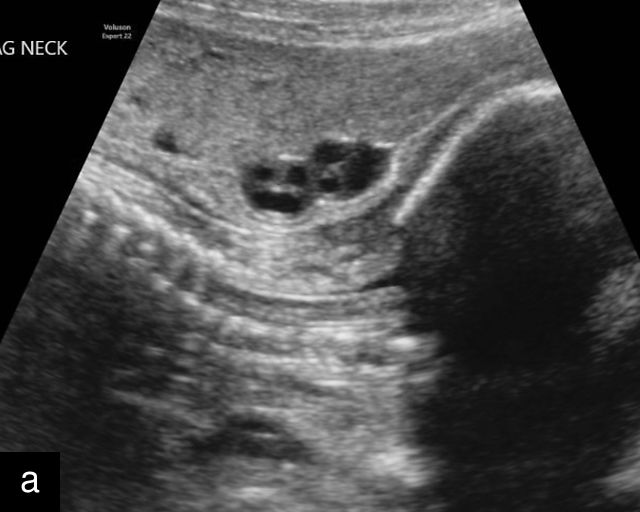

Normal anatomy, development and ultrasound appearance

The umbilical cord serves as the lifeline connecting the fetus to the placenta. It arises from the midportion of the fetal abdomen and typically inserts into the center of the placenta (Figure 16). The average length of the umbilical cord is approximately 55 cm (22 inches).185 It contains three vessels: two arteries, which originate from the fetal left and right internal iliac arteries, and one vein, collectively referred to as a three-vessel cord.

16

Normal appearance of the umbilical cord with two umbilical arteries and a single vein. (a–c) Cross-section of the umbilical cord on grayscale (a,b) and power Doppler (c) ultrasound. In the normal cord, three vessels are visible: a larger umbilical vein and two smaller umbilical arteries. This characteristic appearance is often referred to as the 'Mickey Mouse' sign, the larger circle (umbilical vein) representing Mickey’s face while the smaller circles (arteries) form his ears. (d–g) Grayscale (d) and color Doppler (e–g) images of transverse section of the lower fetal abdomen showing the two umbilical arteries diverging around the fetal bladder. (h) Longitudinal ultrasound view with color Doppler of a normal umbilical cord showing three vessels present in each coil: two arteries with flow in one direction and a single vein with flow in the opposite direction.

The umbilical vein carries oxygenated blood from the placenta to the fetus, while the two umbilical arteries return deoxygenated blood and waste products from the fetus to the placenta for exchange with the maternal circulation. These vessels are surrounded and protected by Wharton’s jelly, a specialized connective tissue derived from the extraembryonic mesoblast, which cushions the vessels and prevents compression. As the umbilical cord approaches its placental insertion, the two arteries form Hyrtl’s anastomosis, a connection that helps equalize blood flow between the arteries.

At a minimum, the mid-trimester ultrasound should include identification and documentation of the umbilical cord's fetal and placental insertions, as well as the number of cord vessels.66,186,187 In a transverse grayscale section of the cord, the two umbilical arteries can be visualized alongside the larger, thinner-walled umbilical vein, creating a characteristic ‘Mickey Mouse’ appearance (Figure 16a–c). Additionally, in a transverse section of the lower fetal abdomen, the umbilical arteries are seen encircling the fetal bladder. This can be seen on grayscale ultrasound and confirmed with color flow Doppler (Figure 16d–g).